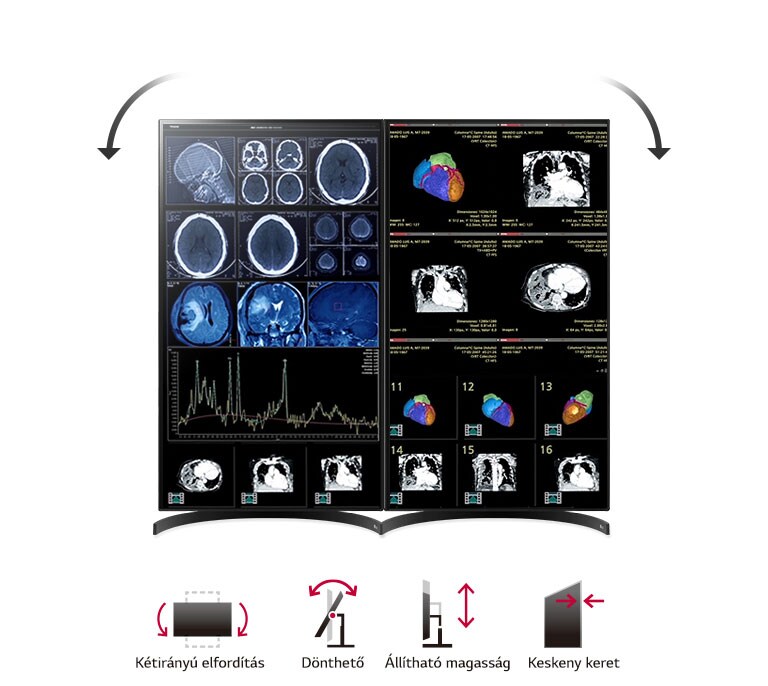

- Ergonomikus, professzionális kialakítás

Az ergonomikus kialakítás lehetővé teszi a magasságban, döntésben és elforgatásban történő testreszabást, így a monitor hosszabb vizsgálatok során is kényelmesen használható.

Ergonomikus kialakítás – a kényelem és fókusz szolgálatában

A két irányban forgatható, ergonomikus talp és a vékony keret biztosítja az optimális diagnosztikai munkaterületet. Az LG 32HL512D lehetővé teszi, hogy a monitorokat álló helyzetben helyezze el egymás mellett, így a részletek könnyen áttekinthetők, a hosszú munkafolyamatok pedig kényelmesebbé válnak.

Ergonómia: Állítható magasság, dönthető panel hosszabb munkavégzéshez

Kijelző pozíciója: Dönthetőség / Magasságállítás / Pivot

| Kényelem | dönthető / kétirányú elforgatás / állítható magasság / keskeny keret |